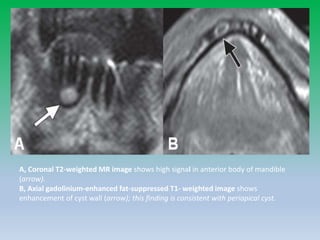

A, Coronal T2-weighted MR image shows high signal in anterior body of mandible

(arrow).

B, Axial gadolinium-enhanced fat-suppressed T1- weighted image shows

enhancement of cyst wall (arrow); this finding is consistent with periapical cyst.